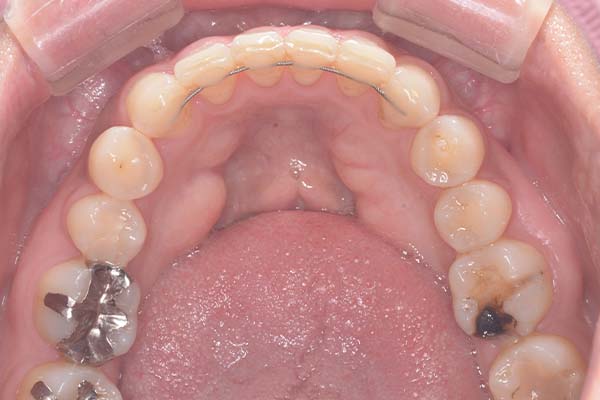

患者様の要望奥歯にインプラント治療したい

治療期間4ヶ月

治療費用880,000円

治療内容左上奥歯に2本インプラント埋入

治療のリスクネジが緩む可能性あり